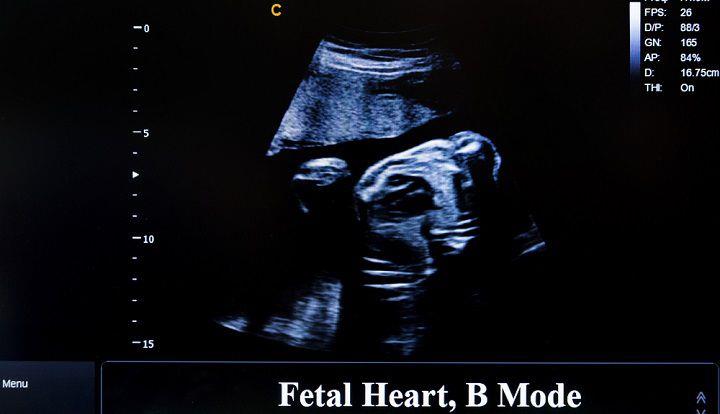

אקו לב עוברי הוא בדיקת אולטרסאונד המבוצעת עם מכשור מתקדם שעוזר באבחון של חריגות לב עובריות. במהלך הבדיקה ייבחנו חדרי הלב וכלי הדם הנכנסים ויוצאים מן החדרים, וזאת כדי לאבחן חריגות בלב. המטרה החשובה ביותר היא לזהות מקרים של פגמים מבניים בלב העובר, הפרעות בקצב הלב והיבטים תפקודיים אחרים של לב העובר[5].

אקו לב עוברי דומה לאולטרסאונד הריון והוא יכולה להתבצע באמצעות מתמר על הבטן או דרך הנרתיק (אולטרסאונד טרנס-ווגינלי). באולטרסאונד בטן יונח מניח ג'ל שקוף על בסיס מים על הבטן, והוא יוזז על פני האזור. המכשיר שולח גלי קול שיוצרים תמונה של לב העובר על מסך. באולטרסאונד טרנסווגינלי, הבדיקה נעשית בתוך הנרתיק. בדיקה זו יכולה להיעשות מוקדם יותר בהריון והיא מייצרת תמונה ברורה יותר מאשר אולטרסאונד בטן[6].